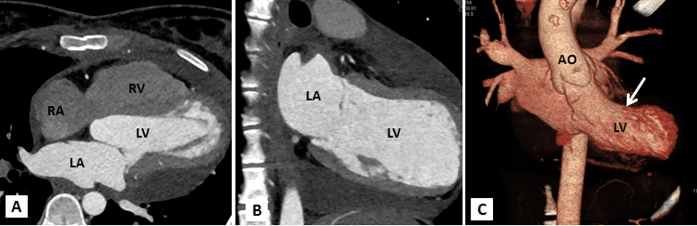

Figure 3A-3C: Computed tomography with multiplanar reconstructions (A and B) and volume rendered image (C) demonstrating a giant left atrial appendage aneurysm with a wide neck. It confirmed that the left sided cardiac prominence corresponds to the left atrial appendage (LAAA).

Multi-slice row computed tomography and magnetic resonance imaging was done that showed a large contrast-enhancing chamber continuous with the left atrium via a wide neck. The left atrium was grossly normal in size itself and a wide neck of 4.0 cm lead to a large aneurysm measuring 8.33 x 7.01 x 4.0 cm. The left anterior interventricular coronary artery was closely seen in relation to the communicating neck and was normal as were the other coronaries. Lower down, the aneurysm was lying adjacent to the lateral wall of the left ventricle which showed normal wall thickness and cavity size. The pulmonary veins were located at their normal anatomical positions with no evidence of stenosis (Figures 3A-3C, 4A, 4B). Considering the size of the left atrial appendage aneurysm with supraventricular arrhythmias and deteriorating clinical symptoms, the patient was medically stabilised and was considered for aneurysectomy of the left atrial appendage. The operation was performed under normothermic cardiopulmonary bypass using angled venous cannulae (Edwards Life Sciences Research Medical Inc, West Midvale, Utah) into the superior and inferior caval veins and aortic cannulation. St.Thomas-II cold blood cardioplegic solution (1:4) and topical hypothermia was used for myocardial preservation. The right pleural cavity was opened, and the heart was dislocated within the right pleural cavity.